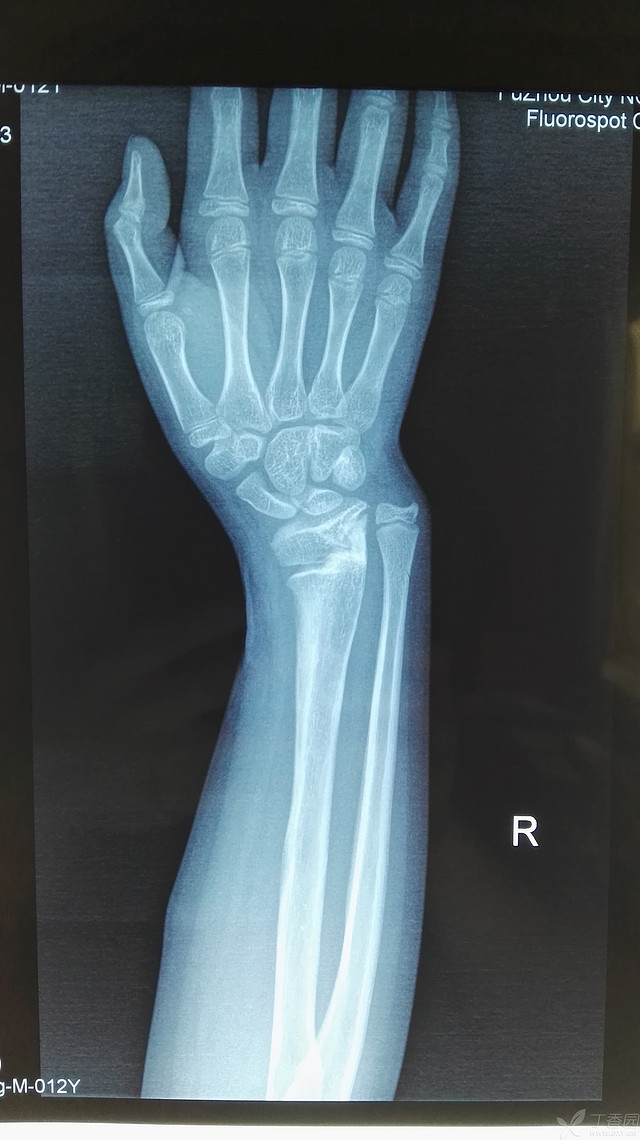

讨论马德隆畸形

马德隆畸形,经石膏固定愈后佳

左右手腕马德隆畸形

马德隆氏畸形:尺桡骨远端发育畸形,尺桡 关节半脱位,腕关节前躬.